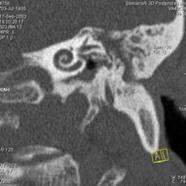

намного сокращается. Например, КТ легких проводится за 20-30 секунд. Рис. 6 на

примере исследования пирамиды височной кости иллюстрирует принцип копьютерной

томографии высокого разрешения. Применены тонкие срезы (0.5 мм) и

"острый" алгоритм реконструкции (кернель 90). (Слева) отчетливо видны

элементы внутреннего уха - улитка, полукружные канальцы. (В центре) показана

проекция продольного сечения височно-нижнечелюстного сустава. (Справа) -

холестеатома.

Рисунок6 -Принципы компьютерной

томографии высокого разрешения (КТВР) на примере исследования пирамиды височной

кости.